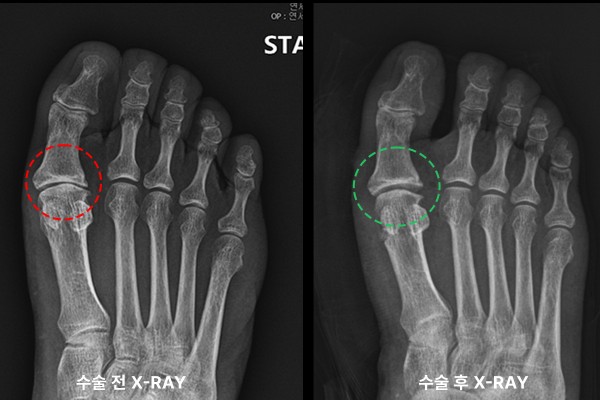

수술 후 X-RAY를 보면 관절 간격이 회복됨이 확인됩니다.

수술 전/후를 비교해보면 엄지관절 간격이 넓어짐을 한 눈에 확인할 수 있습니다.